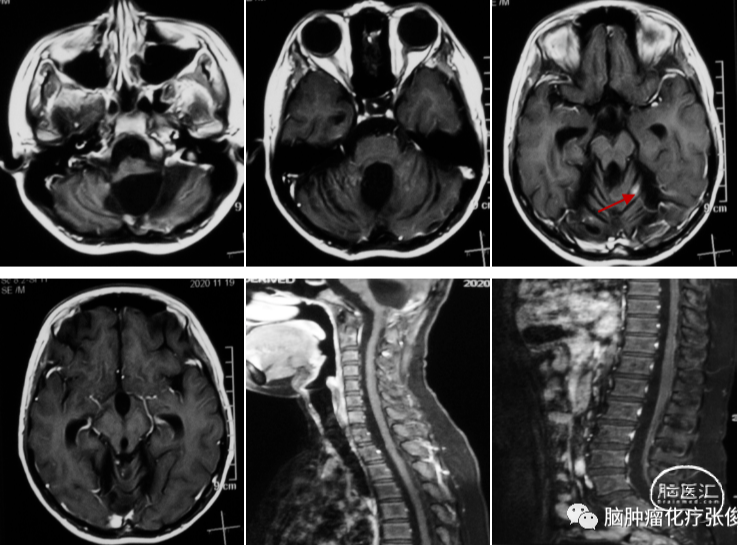

患者董xx,男,14岁。2019年年初患者出现恶心呕吐,未重视。2019年4月患者出现头痛,遂行头部MRI示:双侧小脑半球、蚓部、四叠体区占位。患者于2019-4-16接受手术治疗,手术顺利,术后病理提示髓母细胞瘤,WHOⅣ级。分子分型示:偏向Group4型。患者颅内及脊髓伴有播散病灶,且术后出现缄默,遂行4周期ICE方案化疗,化疗后复查核磁提示颅内、髓内病灶缩小、减少。2019年8月接受了全中枢放疗,放疗后继续化疗4周期,末次化疗时间:2020-2-26。2020-3-17复查头颅及全脊髓核磁提示病灶基本消失。停止治疗,定期随访核磁。2020-7-2复查核磁提示肿瘤复发,颅内、全脊髓多发异常强化影如(见下图)。

结合患者病史,化疗结束后4月余即出现肿瘤复发,肿瘤进展快,给予更换方案化疗,具体用药为:替莫唑胺+依托泊苷+阿帕替尼。化疗2周期后,2020-9-17复查头颅及全脊髓核磁提示颅内病灶明显减少,疗效评价:PR。患者目前仍在化疗中,2020-11-18复查核磁提示仅余左侧小脑半球小点状强化影(见下图)。